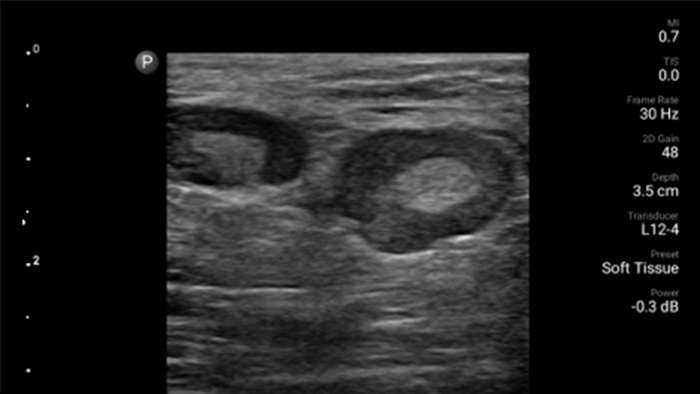

Esté atento a la neumonía por COVID

Lumify puede ayudar a obtener resultados similares a los de una tomografía computarizada de tórax al evaluar la neumonía y el síndrome de dificultad respiratoria en adultos.

• Rango extendido de frecuencias de operación entre 12 y 4 MHz • Tamaño de apertura: 34 mm • 2D, Doppler orientable a color, Modalidad M, XRES avanzado e imágenes armónicas multivariables, SonoCT • Imágenes de alta resolución para aplicaciones superficiales: tejidos blandos, vasculares, superficiales, musculoesqueléticos y pulmonares • Marcador de línea central • Transductor USB-C con cable reemplazable